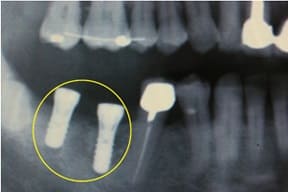

CASE03 臼歯部インプラント ~ブリッジがグラつき始めている~

ブリッジの部分の下顎の骨が吸収をおこし、ブリッジで支えている歯がぐらつき始めている状態。予後を考えた結果、ブリッジで支えることが困難という診断のもと、インプラント治療を施したケースです。